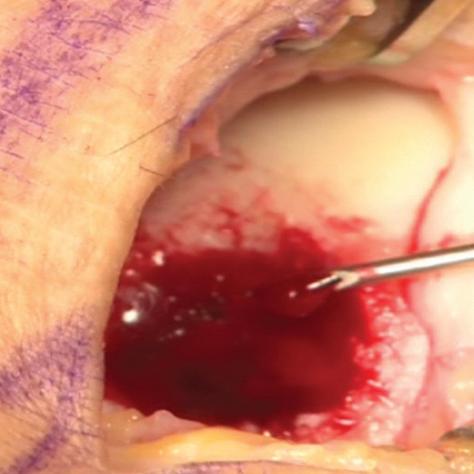

The arthroscopic images taken during a BST-CarGel surgery. The original lesion before BST-CarGel treatment.

The repaired lesion at the 13-month 2nd look arthroscopy. The delivery of BST-CarGel in a cartilage lesion.

The technology itself is simple: an implant, made of a chitosan solution and buffer, is mixed with autologous blood and applied to lesions. What makes it unique is that this combination stimulates the body to regenerate its own cartilage, and may indeed be pioneering an entirely new way to treat damaged joints.

Europe (it is not yet approved in Canada). It is applied as a one-step procedure by combining two components — a chitosan solution and a buffer which are then mixed with fresh autologous whole blood - just before its application to a lesion surgicallyprepared by bone marrow stimulation, such as microfracture.